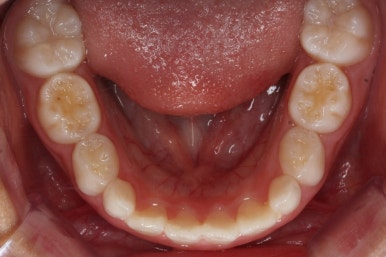

유지단계 4개월째의 모습입니다.

거꾸로 물리는 반대교합이 재발되지 않고 자리를 잘 잡고 있습니다.

위턱뼈가 넓어지다보니 처음에는 삐뚤었던 앞니도 자연스레 자리를 잡아가고 있습니다.

유지단계 11개월 경화 후의 모습입니다. 유지상태는 상당히 좋네요.

이제 유지장치도 종료하기로 하고, 앞으로는 주기적으로 아래턱이 자라나지 않는 지를 체크하게 될거에요.